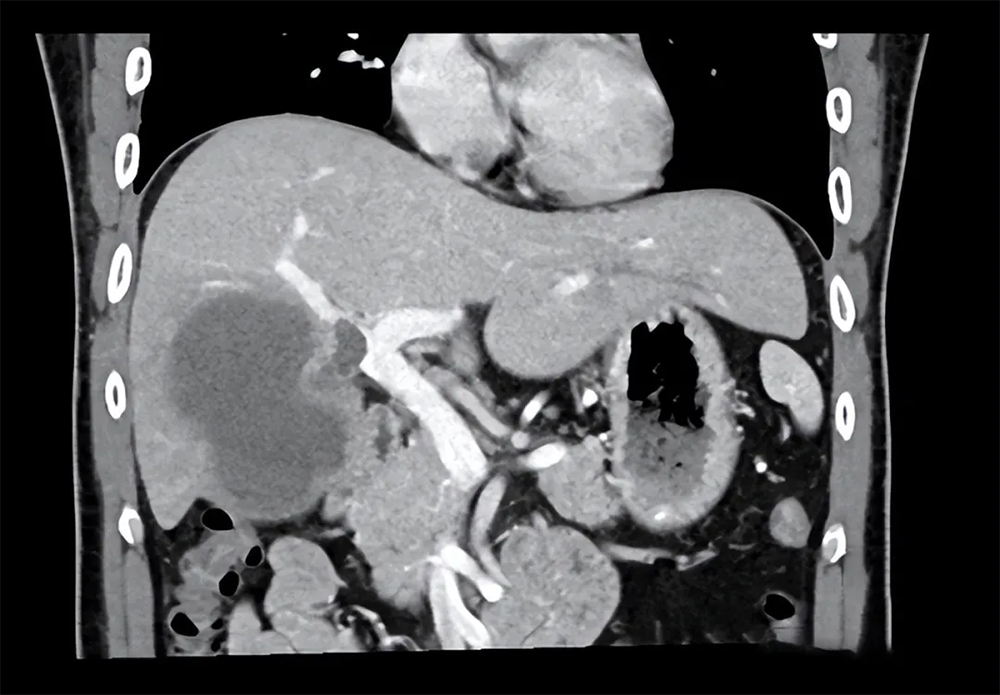

患者李先生21年被确诊肝癌晚期,由于肿瘤较大,正常肝脏已经不足30%,如果切除,剩余肝功能无法支撑人体的正常需求,加上肿瘤已经侵犯血管,形成癌栓,并且逐渐向脾脏出现转移,经医生评估后认为已经无法通过手术切除肿瘤。

在经过治疗后:复查肿瘤体明显萎缩,肿瘤相关生物指标也在不断下降。到2022年4月份复查CT,肿瘤总体积已经缩小了一半多,剩余肝脏体积也明显增加。

最终经过医生评估,认为李先生的身体情况良好,可以耐受手术,最终在全麻插管下行腹腔镜脾切除+巨大肝癌切除+胆囊切除术+门静脉切开取栓术,将体内病灶切除。